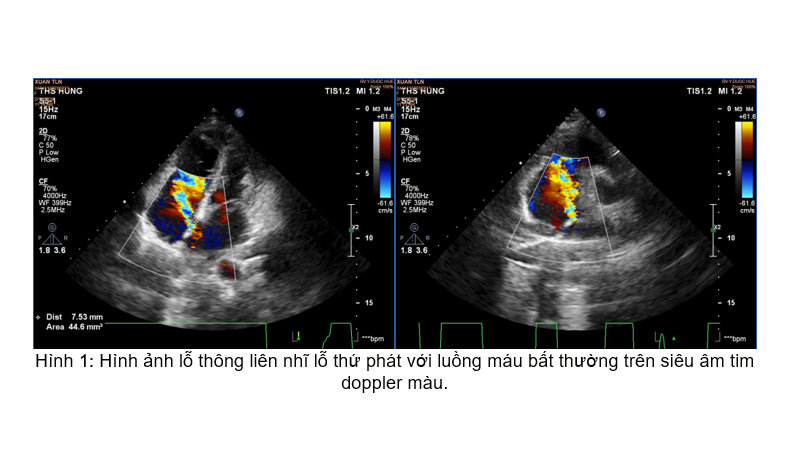

Với triệu chứng hồi hộp, khó thở từng cơn, hạn chế hoạt động gắng sức xuất hiện và tăng dần trong vòng 01 tháng gần đây. Bệnh nhân đã được làm đầy đủ các xét nghiệm, siêu âm tim và đã phát hiện 01 lỗ thông liên nhĩ thứ phát, đường kính 14 mm.

Xác định đây là nguyên nhân gây ra các triệu chứng trên bệnh nhân cũng như khảo sát kỹ cho thấy hình thái cấu trúc, chức năng tim phù hợp, bệnh nhân đã được chỉ định điều trị bằng phương pháp đóng lỗ thông liên nhĩ bằng dù Amplatzer ASD Occluder đường kính 18 mm qua da bằng dụng cụ dưới hướng dẫn của hệ thống tăng sáng số hóa xóa nền và siêu âm tim doppler màu.